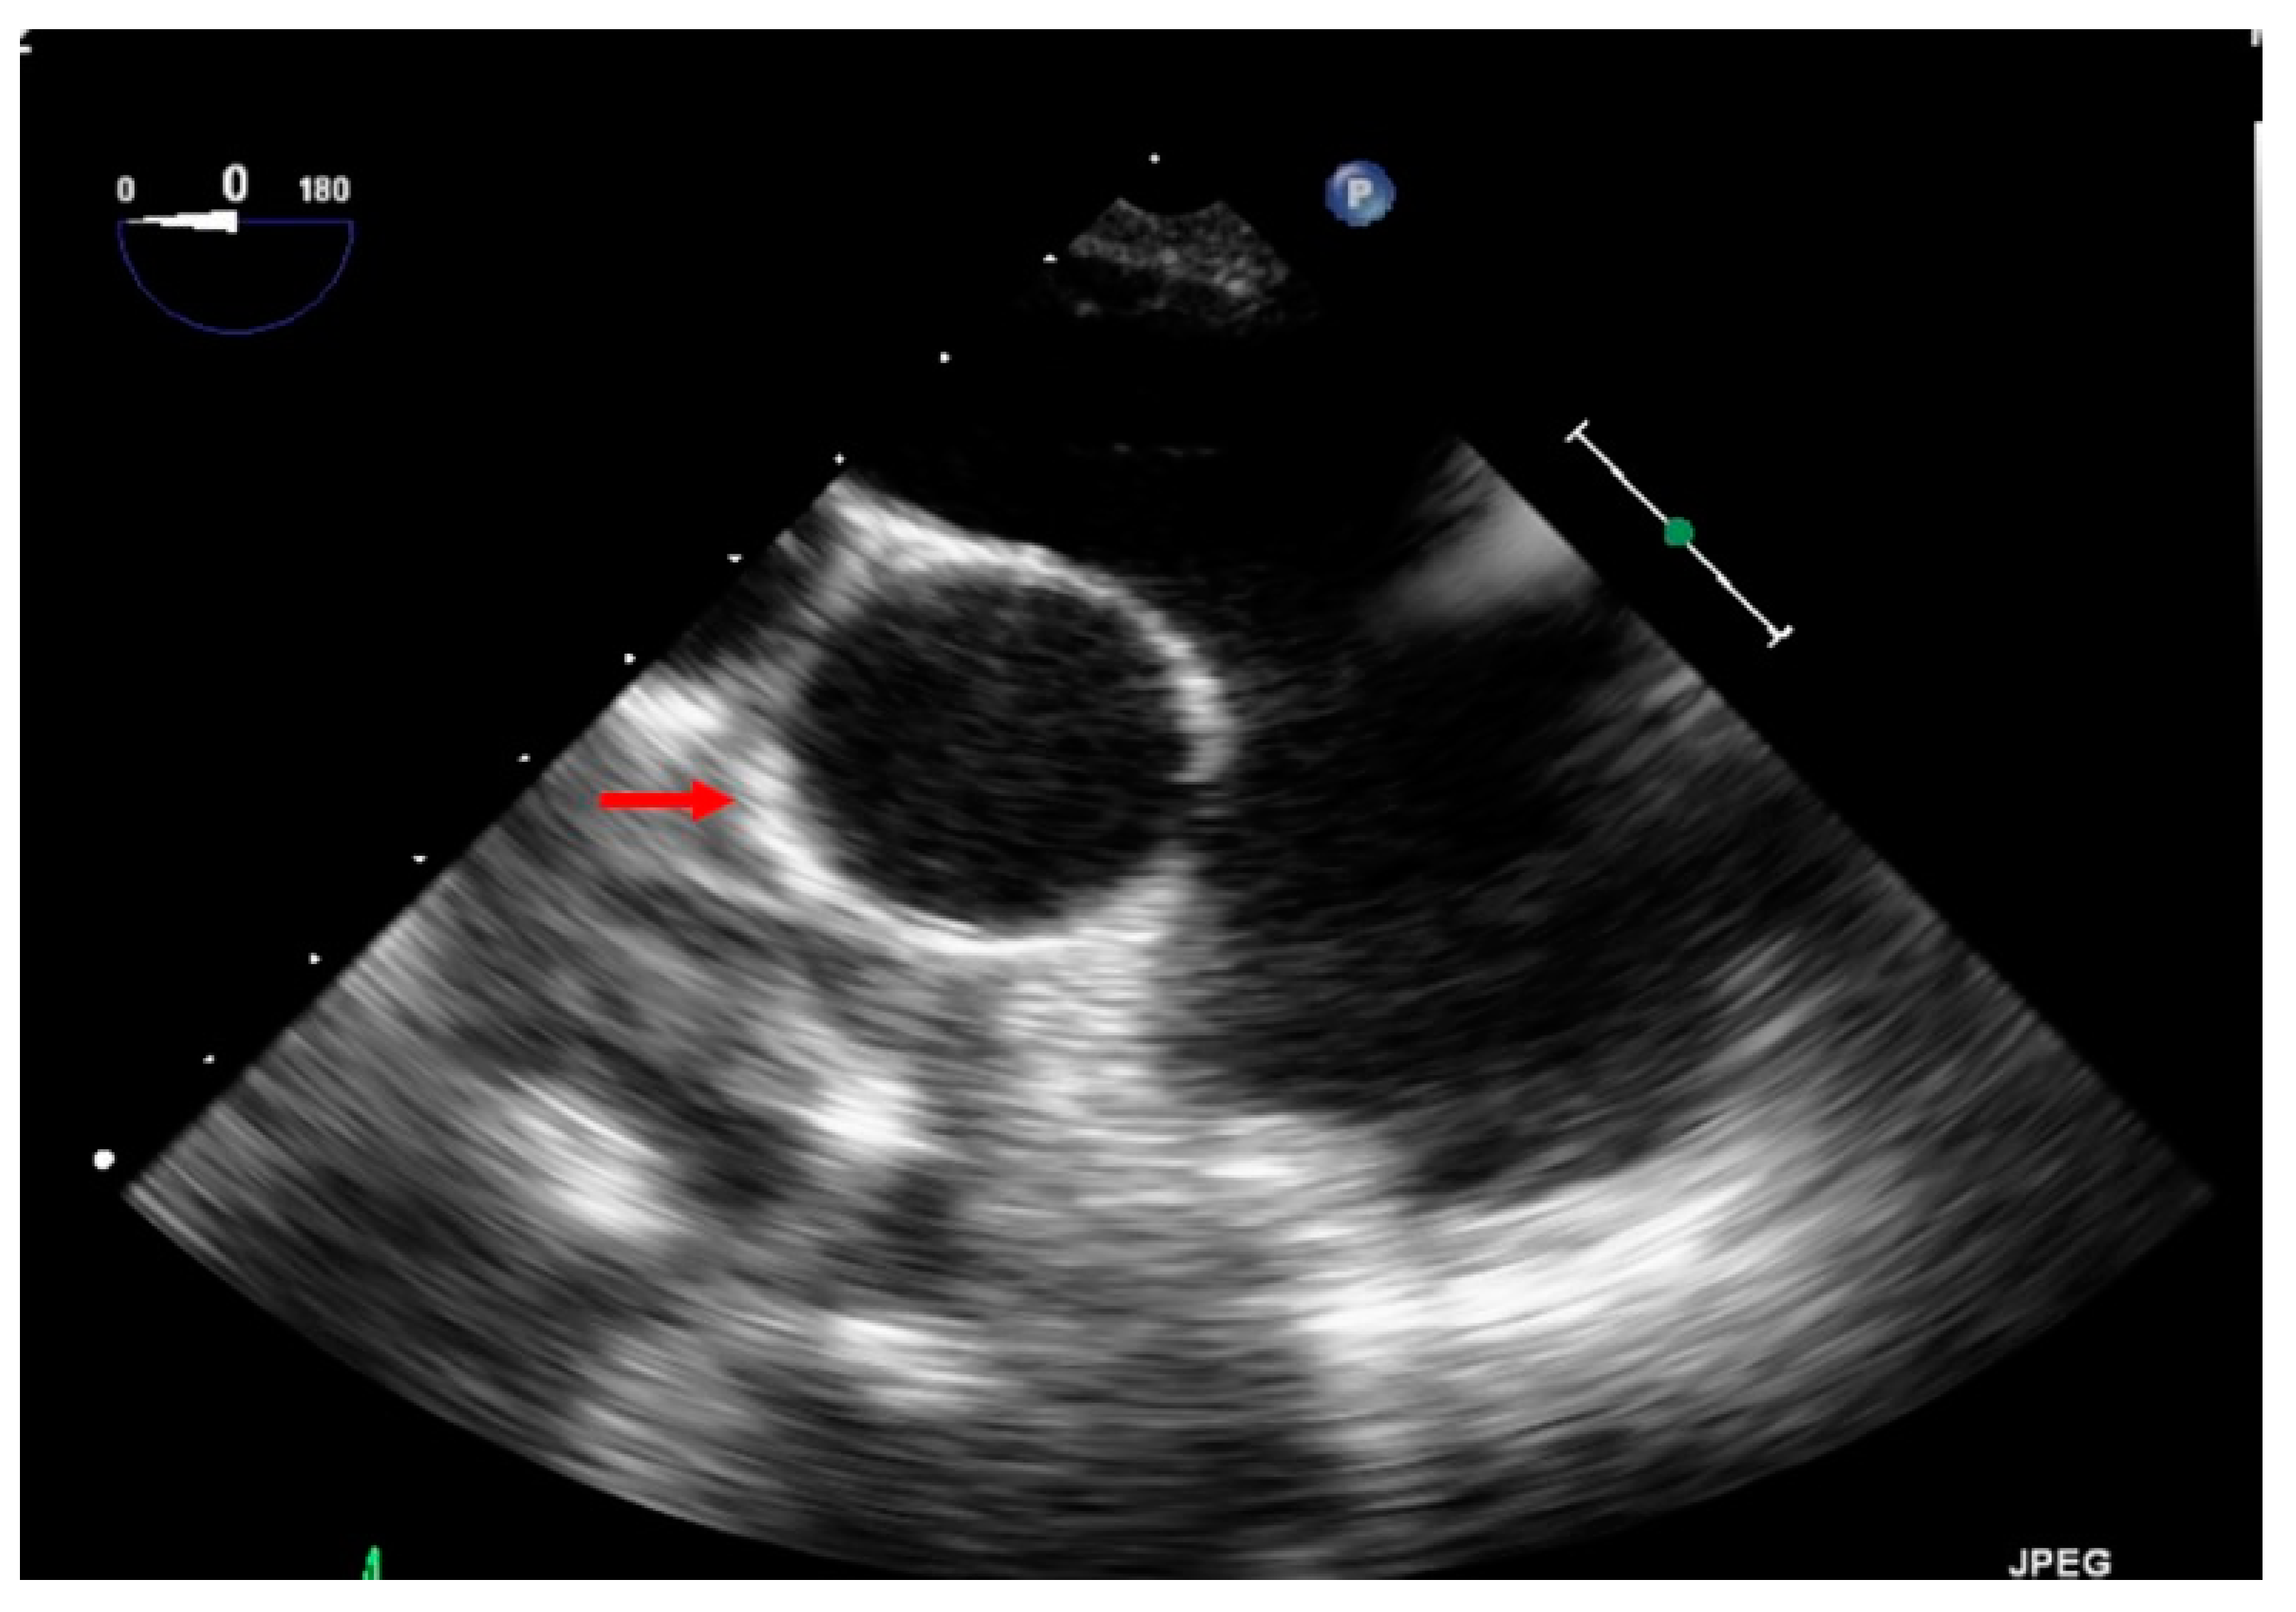

3.5. Transthoracic Echocardiography